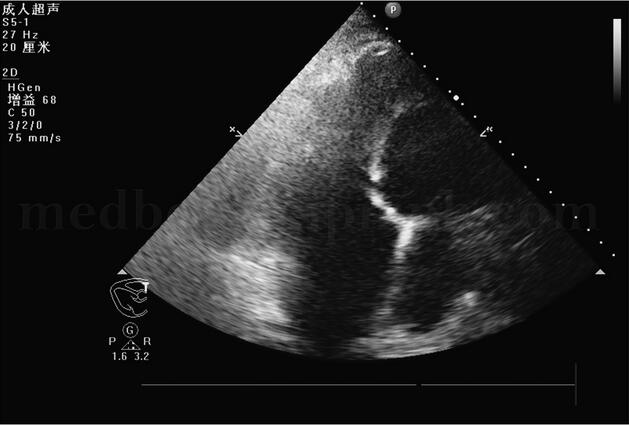

胸部X线片(图003‐1)示:肺水肿并双下肺感染改变;心尖部钙化,不除外室壁瘤可能;双侧胸腔积液,右侧叶间积液;右上肺高密度影。生化结果:心肌酶、肝肾功能正常。D‐二聚体:3129μg/L(0~300)。心电图(图003‐2)示:窦性心动过速,右束支传导阻滞,陈旧性前壁心肌梗死。超声心动图(图003‐3~图003‐5)显示室间隔破裂穿孔(因血栓封堵,无分流):室间隔中间可见两处回声缺失,直径均约为0.4cm,其左室面血栓形成。彩色多普勒:未见明确过隔分流。左室腔中间‐心尖段可见两块不规则形中低密度团块影附着,团块部分相互连接,两团块大小分别为5.4cm×2.95cm、6.1cm×1.23cm。

图003‐3 超声心动图1